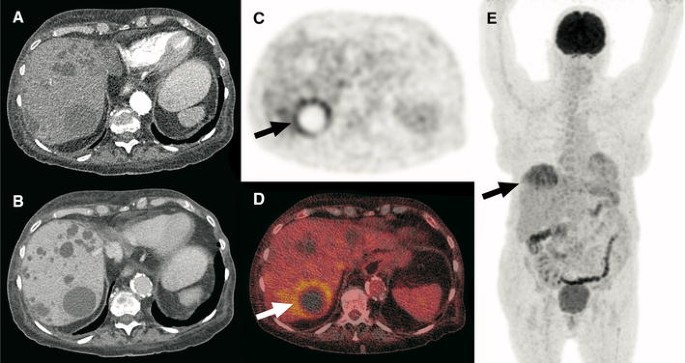

A 61-year-old man with ADPKD and unilateral renal agenesis was admitted to the hospital because of a possible urinary tract infection. He presented with complaints of cold shivers, pollakiuria, stranguria, lower abdominal pain and cloudy urine. Blood tests showed a CRP level of 363 mg/L and a white blood cell count of 6.6 × 109/L, while a urine culture tested positive for Escherichia coli. The patient’s clinical condition improved under ciprofloxacin treatment, but his CRP level remained high 5 days later at 154 mg/L. Because of the possibility of pyelonephritis or cyst infection, ultrasound was ordered. Ultrasonographic images of the liver (a) and kidney (b) showed multiple cysts, but no hydronephrosis and no potential site of infection. Subsequently, FDG-PET/CT was performed. Axial FDG-PET (c), low-dose CT (d), fused FDG-PET/CT (e), and coronal maximum intensity projection FDG-PET (f) showed pathologic FDG uptake of the wall of a cyst in the right kidney (arrows), consistent with cyst infection. No pathologic FDG-avid foci were detected elsewhere. The patient was discharged 1 day after the FDG-PET/CT scan in good clinical condition, where he continued his course of ciprofloxacin for 10 more days